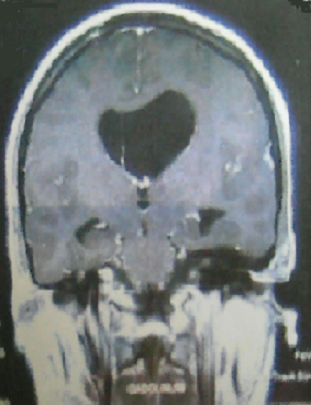

La sarcoïdose systémique est une maladie ganulomateuse qui touche avec prédilection le poumon et le médiastin. Elle peut s'accompagner de complications graves particulièrement neurologiques. L'hypertension intracrânienne est rarement révélatrice de cette pathologie. Patiente âgée de 35 ans a consulté pour des céphalées, des vomissements, une xérostomie et des troubles de la marche. L'examen physique a objectivé un syndrome cérébelleux. L'examen biologique a retrouvé un syndrome inflammatoire, un taux élevé de l'enzyme de conversion de l'angiotensine, une calcémie et une calciurie normales, un bila rénal et hépatique sans anomalies. La tomodensitométrie cérébrale a révélé une hydrocéphalie avec dilatation du ventricule latéral gauche. L'IRM cérébrale a retrouvé cette dilatation associée à la présence d'un granulome ayant un aspect d'hypersignal en T2 et obstruant partiellement le trou de Monro gauche. L'étude du liquide céphalo-rachidien a montré une hyperprotéinorrachie avec une cytologie normale. Les diagnostics de tuberculose, sarcoïdose et lymphome ont été suspectés. L'examen anatomopathologique des biopsies labiales et trans-bronchiques étagées a conclut à la présence de granulomes épithéloïdes et giganto-cellulaires sans nécrose caséeuse. La recherche de bacille acido-alcoolo-résistant par la coloration de Ziehl-Neelson était négative. La culture sur milieu de Lobstein ainsi que l'intradermo-réaction à la tuberculine étaient aussi négatives. Le diagnostic de sarcoïdose systémique compliquée d'une atteinte neurologique a été retenu. Par ailleurs les explorations fonctionnelles respiratoires, le scanner thoracique et le lavage alvéolaire étaient sans anomalies. Le traitement s'est basé sur une corticothérapie associée à des boli de cyclophosphamide. L'évolution était favorable sur le plan clinique et radiologique.